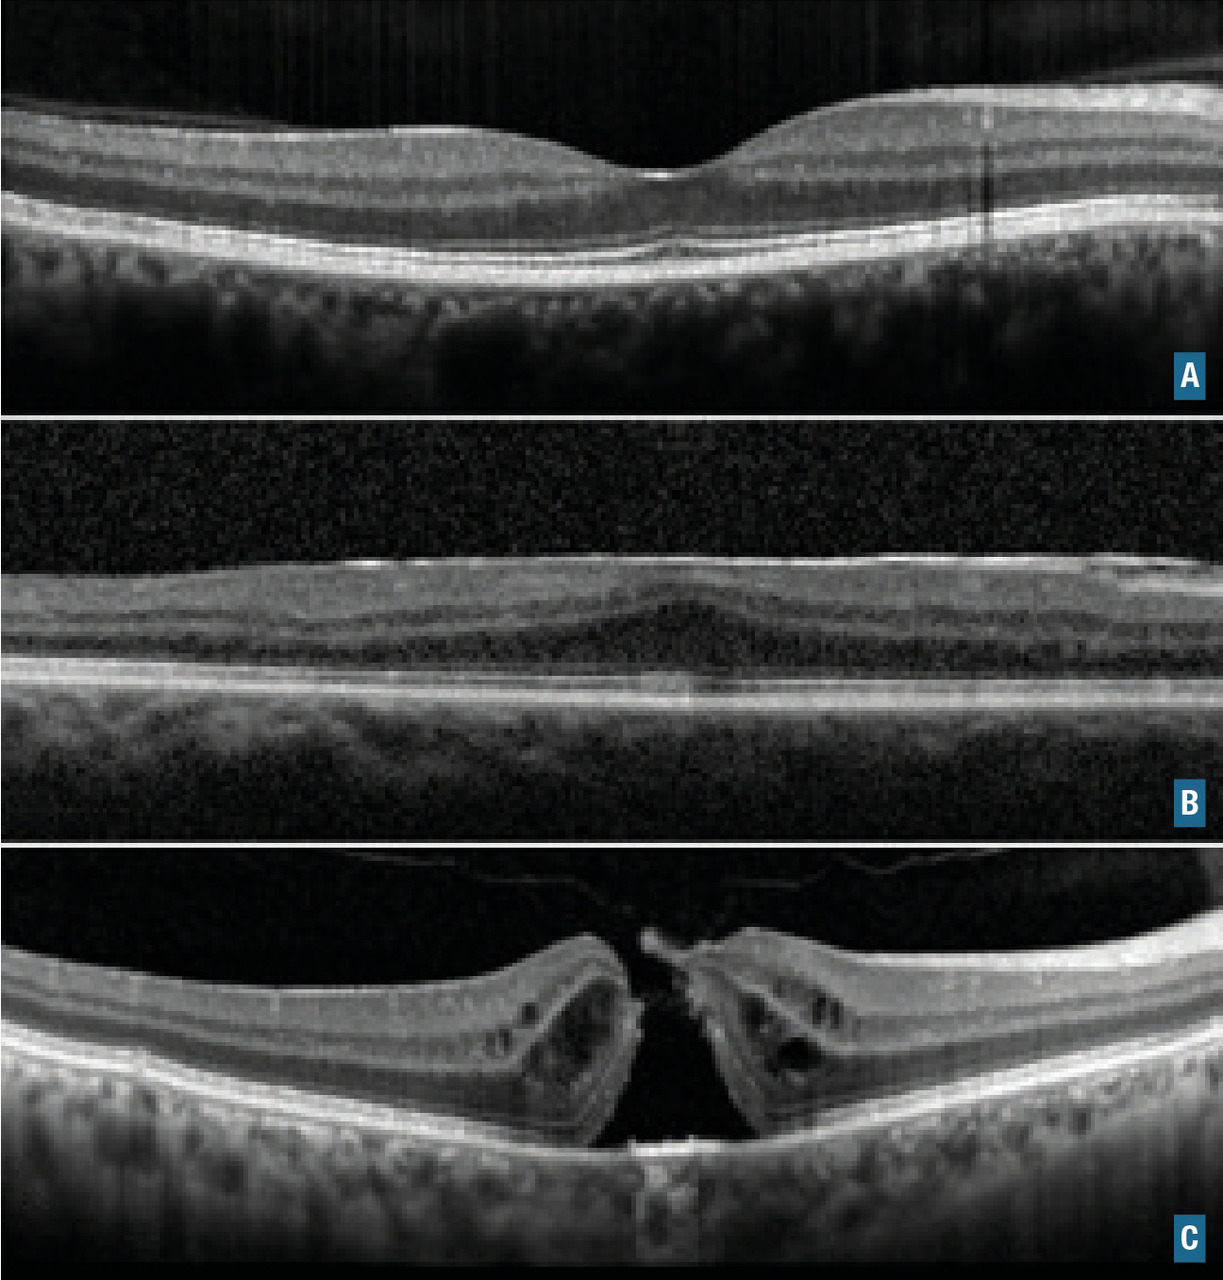

Membrane épimaculaire et trou maculaire

Ce sont des pathologies de l’interface vitréorétinienne (fig. 11). Les signes fonctionnels constituent le syndrome maculaire : métamorphopsies, baisse d’acuité visuelle et/ou scotome central. Le diagnostic est fait à l’examen du fond d’œil (« reflet cellophane » pour la membrane) et confirmé par l’examen en OCT. La prise en charge thérapeutique est chirurgicale.

Ce sont des affections rétiniennes (fig. 12) d’origine génétique de deux types :

• les dystrophies maculaires avec une atteinte prédominante sur les cônes. La plus fréquente est la maladie de Stargardt, de transmission autosomique récessive ;

• les rétinopathies pigmentaires, qui sont des dystrophies rétiniennes atteignant dans un premier temps les bâtonnets puis généralement les cônes dans un second temps. Il y a plus de 200 mutations décrites à ce jour. Les patients se plaignent d'abord d’une héméralopie (cécité nocturne), puis d’un rétrécissement du champ visuel, avant une baisse d’acuité visuelle.